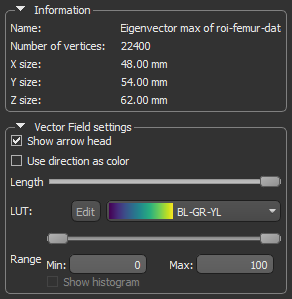

- Uncheck the Show arrow head option. This usually improves the visibility of the vectors in the field.

- Use the Length slider to adjust the length of the vectors.

- Choose another look-up table (LUT) in the LUT drop-down menu.

NOTE The Jet LUT is often a good color scheme choice. In this LUT, vectors corresponding to the highest surface anisotropy are colored red, while those corresponding to the lowest, or are isotropic, are colored blue.

- Threshold the vector field-based map to show only high or low anisotropy areas with the Range slider, as shown below.